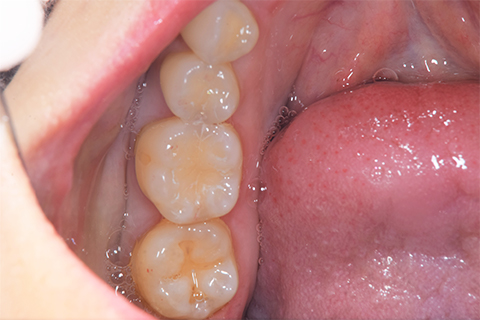

インレー症例

虫歯除去後

In(インレー)セット後

当院では自費のインレー(つめ物)の場合、ゴムのシートをかけてから詰めていきます。

ゴムのシートをすることで、歯面を最大限乾燥することができ、接着力が上がる他、操作時の材料の誤飲の防止、接着剤の歯肉縁下(歯ぐきの中)への侵入を防止するなどといったメリットがあります。(歯の並びによっては、ゴムのシートができないことがあります。また、シートをかけることで苦しくなる、苦手という方には無理に行いません。)

年齢・性別 40代・男性

主訴 左上の奥歯がしみることがある

治療内容 左上4の虫歯

治療期間 2週間

費用 ・ジルコニアインレーで修復

55,000円

治療方針

IOSのNIRI機能によって虫歯部分が明らかになったので、虫歯を除去後に修復治療を行うこととしました。